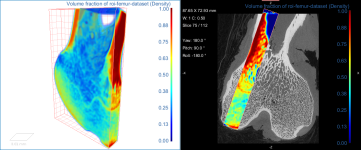

This section of the tutorial describes how to use the Bone Analysis module for 3D volume fraction plotting. You should note that volume fractions are scalar maps.

Comparison of volume fraction scalar map (on left) with vector-based field of anisotropy (on right)

- Choose the settings for the volume fraction map on the Mappings tab, as shown below.

- Examine the volume fraction map in the 3D or 2D views in the workspace.

NOTE In most cases, the Jet LUT provides good visualizations of volume fraction.